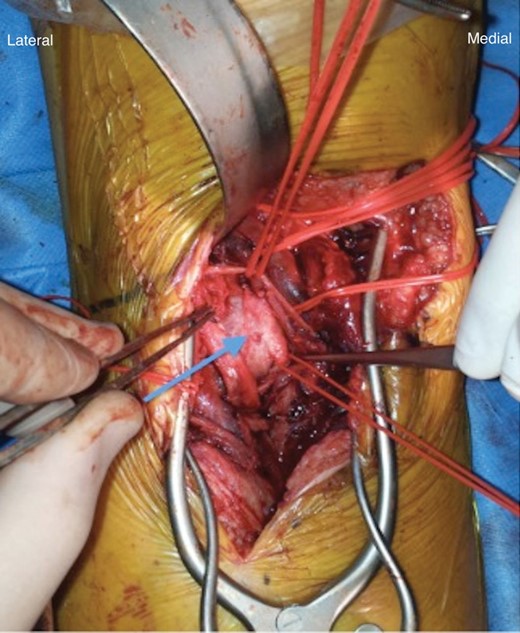

An emergency open repair of the popliteal pseudoaneurysm was undertaken. During the surgery, an S-shaped incision was made in the popliteal fossa. Initial dissection was difficult because of the overlying popliteal vein and tributaries. After achieving proximal and distal control, the pseudoaneurysm was opened and clot was evacuated (Fig. 3). The arterial injury was easily identified at the proximal end of the pseudoaneurysm (Fig. 4) and was closed with a patch of short saphenous vein (Fig. 5).